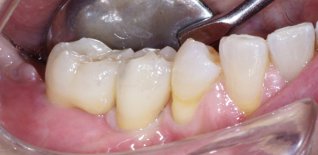

Eseguito innesto d'osso in blocco e dopo circa 4 mesi inserzione degli impianti.

Successivamente sono stati applicati degli elementi dentari.